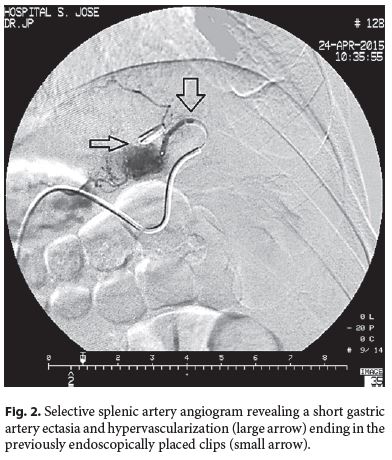

A 28-year-old man without any remarkable past medical history presented with hematemesis and hemodynamic instability. There was no significant past medical history. He denied any medication intake, namely nonsteroidal anti-inflammatory drugs, alcohol abuse, or smoking habits. Upper gastrointestinal endoscopy (UGE) revealed fresh blood and a giant clot covering the gastric body and fundus. Repeated UGE showed no mucosal defect. Radial endoscopic ultrasound (EUS) was performed, indicating a submucosal vessel arising in the greater curvature of the proximal gastric body which identified a Dieulafoys lesion as the possible source of bleeding. Considering clinical stability, EUS-guided therapy with linear scope was planned for the next morning when the scope was available, but rebleeding occurred. UGE was performed with a therapeutic scope, as the site of bleeding was already identified and active bleeding was expected. Thus, the advantages of a dual channel scope, which is more easily maneuvered, would outweigh the advantagesof using the echoendoscope, which has the main benefit when the Dieulafoys lesion cannot be identified on UGE because it is no longer bleeding. UGE revealed an adherent clot in the suspected Dieulafoys lesion location previously described on EUS. After the first clip deployment, massive bleeding occurred. Hemostasis was achieved after adrenalin and polidocanol injection and clipping. EUS was performed to confirm vessel obliteration but still identified a large caliber (2.5 mm) feeding vessel arising from the splenic artery penetrating the gastric muscularis propria (Fig. 1). Selective splenic artery angiogram as determined by EUS was performed, revealing a short gastric artery ectasia and hypervascularization (Fig. 2, large arrow) ending in the previously endoscopically placed clips (Fig. 2, small arrow). Superselective transcatheter arterial embolization (TAE) was performed, and the patient presented no further episodes of gastrointestinal bleeding at the 1-year follow-up.